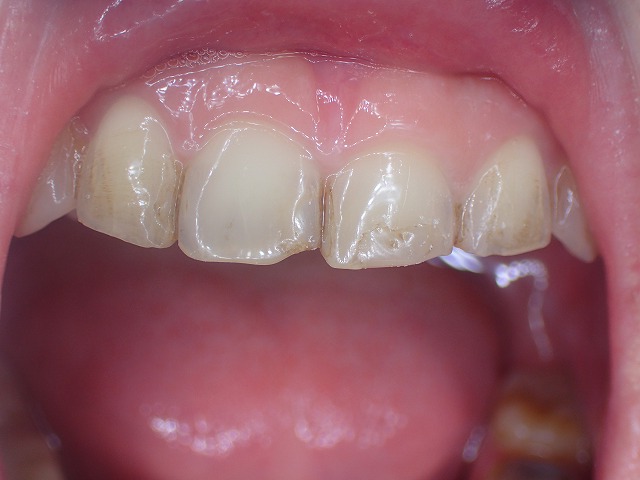

上顎前歯

激しく摩耗している

顎の動きで左右非対称に摩耗しているの

過蓋咬合なので上顎前歯の内側の摩耗が激しい

歯並びが左右非対称

矯正後 過蓋咬合と歯ぎしり もう少し矯正で補正してくれれば

過蓋咬合も歯列矯正で補正できたはず 決して失敗ではないが

過蓋咬合ですので、下の歯に上の歯がかぶさり

下の歯が見えません。